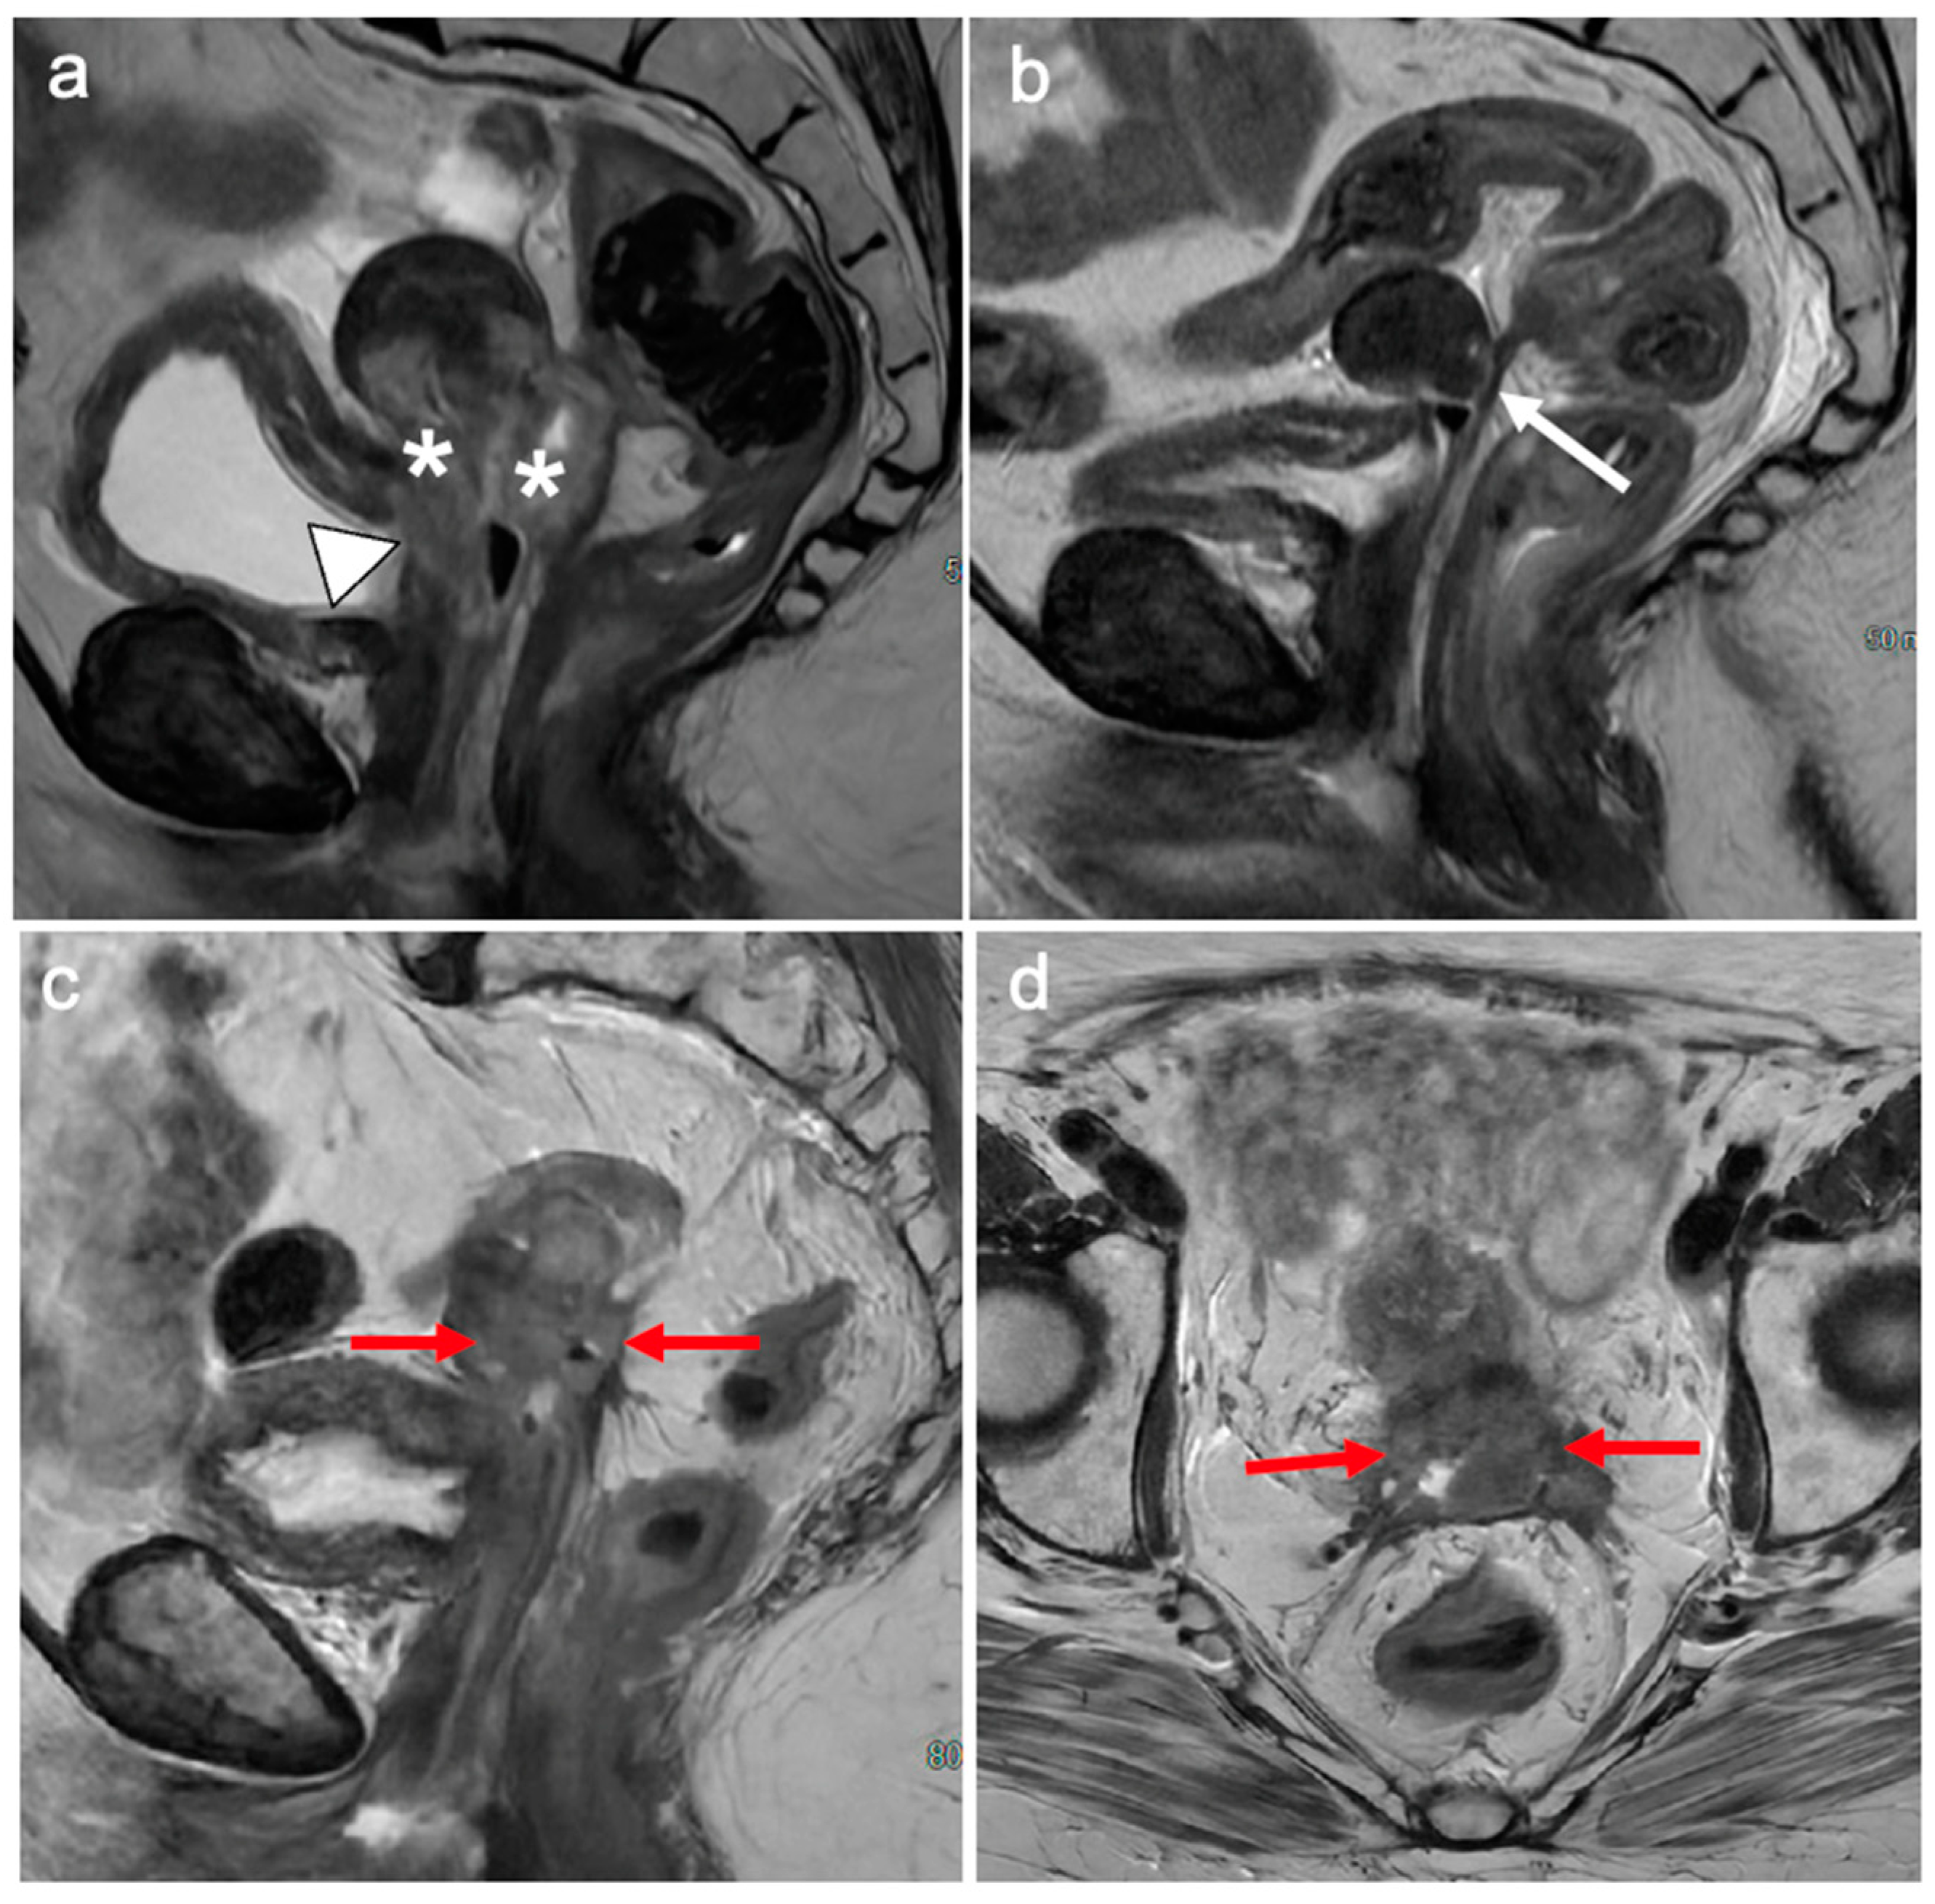

6. FIGO Stage III

7. FIGO Stage IV

8. Impact of MRI Findings on Treatment Selection